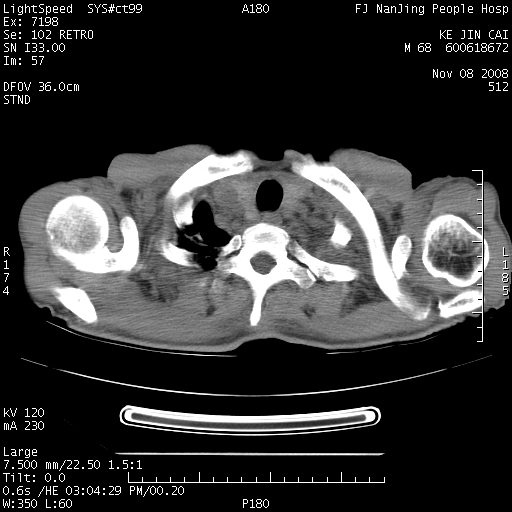

是个很有看头的病例,咋人气那么不旺?没多少人兴趣呢?这个病例几大怪:1   恶性肿瘤侵犯心肌左房怪,心肌一般不会被恶性肿瘤侵犯吧?2   左下肺均匀实变怪,内无含气,有别一般不张实变,含气肺泡完全为液体取代,而非一般不张实变的肺萎陷,冷不丁还以为是肿大的脾脏3   肿瘤本身怪,像tb肺不张4   这么有看头的病例没人气怪。呵呵。

左肺恶性肿瘤侵犯肺动脉,左心房内瘤栓,胸膜转移。

左肺恶性肿瘤侵犯肺动脉,左心房内瘤栓,胸膜转移,少见,学习了。